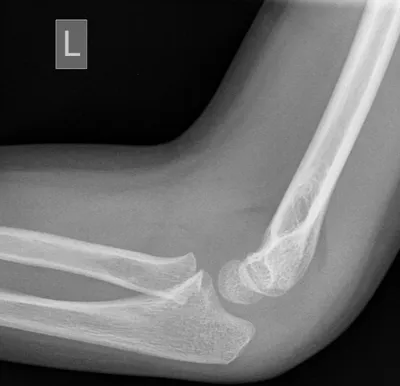

Supracondylar fracture of elbow

Elbow

4/10/2026